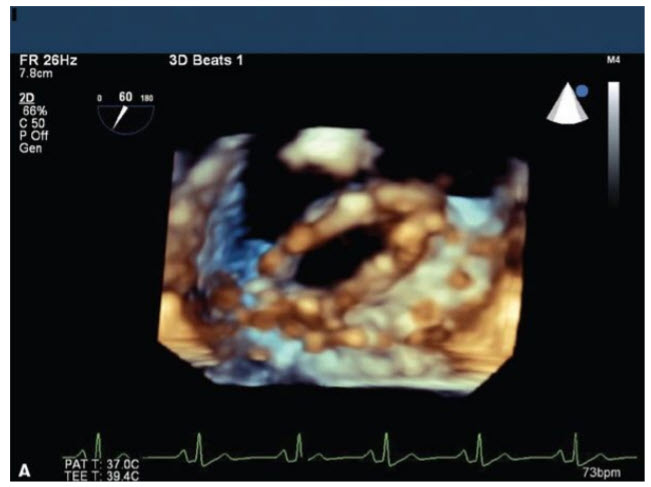

The three-dimensional (3D) transesophageal echocardiographic (TEE) image in Figure below

demonstrates a patient with:

A. Normally functioning bioprosthetic mitral valve replacement (MVR).

B. Normally functioning bileaflet mechanical MVR

C. Mitral valve (MV) endocarditis with a vegetation

D. Abnormal mechanical MVR

E. Abnormal bioprosthetic MVR